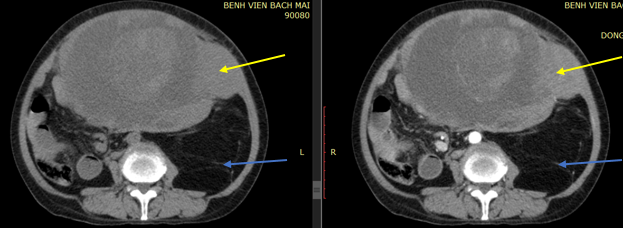

Hình 2: Hình chụp CT ổ bụng trước và sau tiêm thuốc cản quang

Thì động mạch (hình bên phải): Khối ngấm thuốc không đồng nhất, có thành phần đặc - (mũi tên vàng) ngấm thuốc manh và tương đối đồng nhất. Ngoài ra trong khối có các rải, vách tăng tỷ trọng (chưa loại trừ tổn thương xuất huyết - mũi tên xanh).